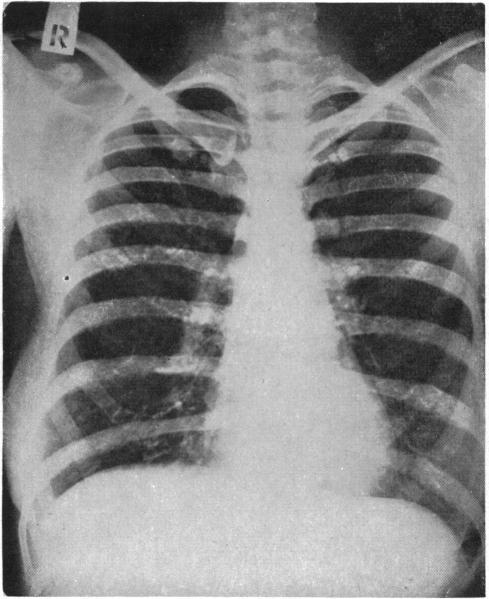

Atypical pneumonia.

Br Med J. 1950 Dec 30;2(4695):1457-61. doi: 10.1136/bmj.2.4695.1457.